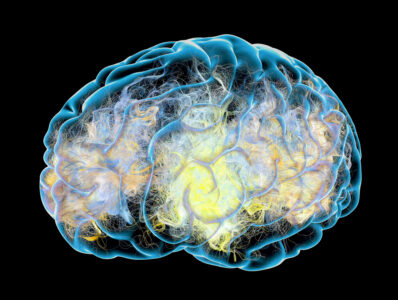

Zjistěte stáří svého mozku: Vyzkoušejte japonský test na vnímání detailů. Dokážete najít všechny skryté prvky?

Proč tělo při usínání sebou škubne? Dle evoluce jev chrání člověka před možným nebezpečím